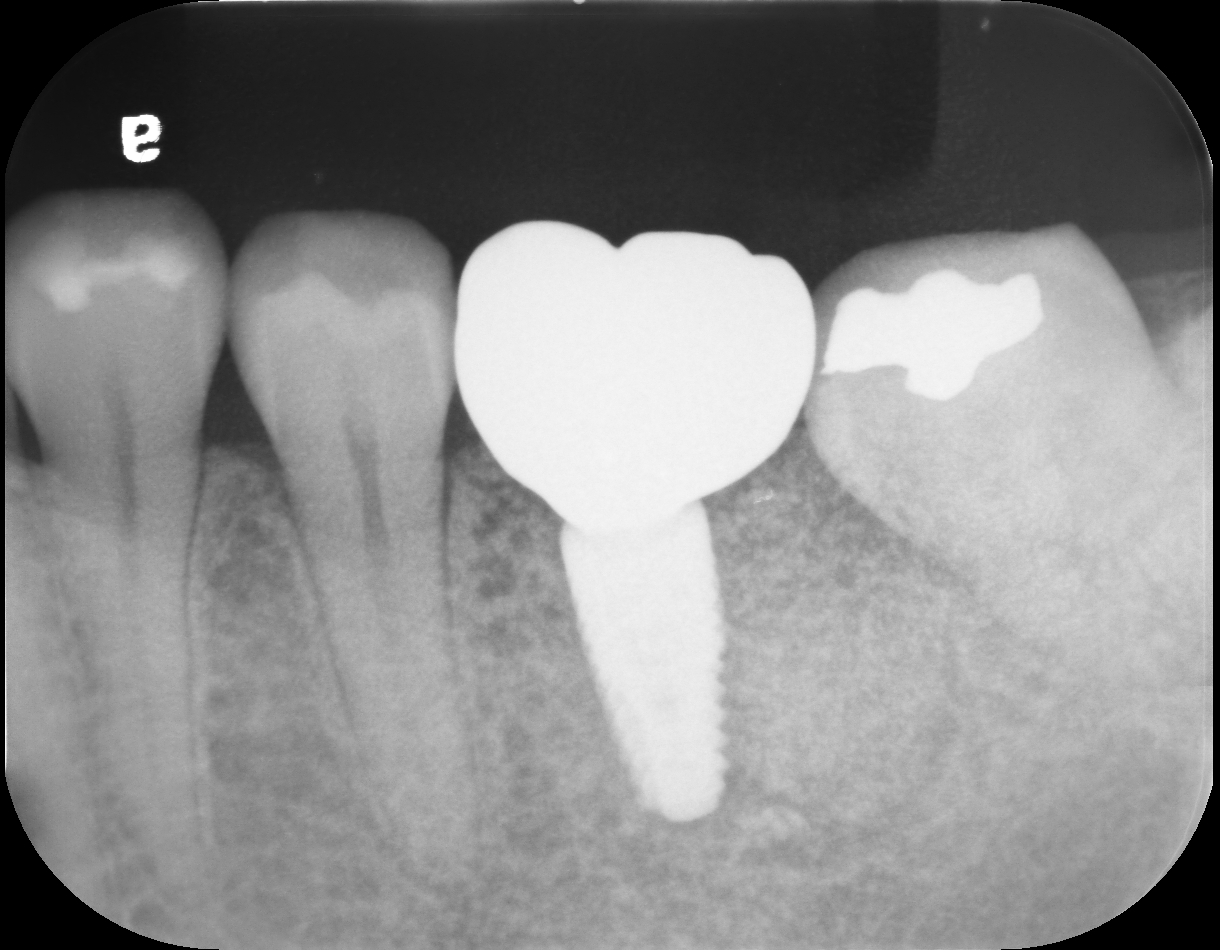

after

今後は、失った歯の機能を回復するための治療を計画していきます。

抜歯後、そのままにしておくと骨がやせてしまう可能性があるため、抜歯したその日のうちに、将来インプラントを入れるための骨を守る処置(歯槽堤温存術)を行いました。

この処置により、骨の量をできるだけ保ち、インプラントの周りの環境を整えることができます。

| 治療内容 | 抜歯、骨造成術、インプラント即時埋入術 |

| 治療期間 | 6ヶ月 |

| 通院回数 | 6回 |

| 費用 | 約600.000円 |